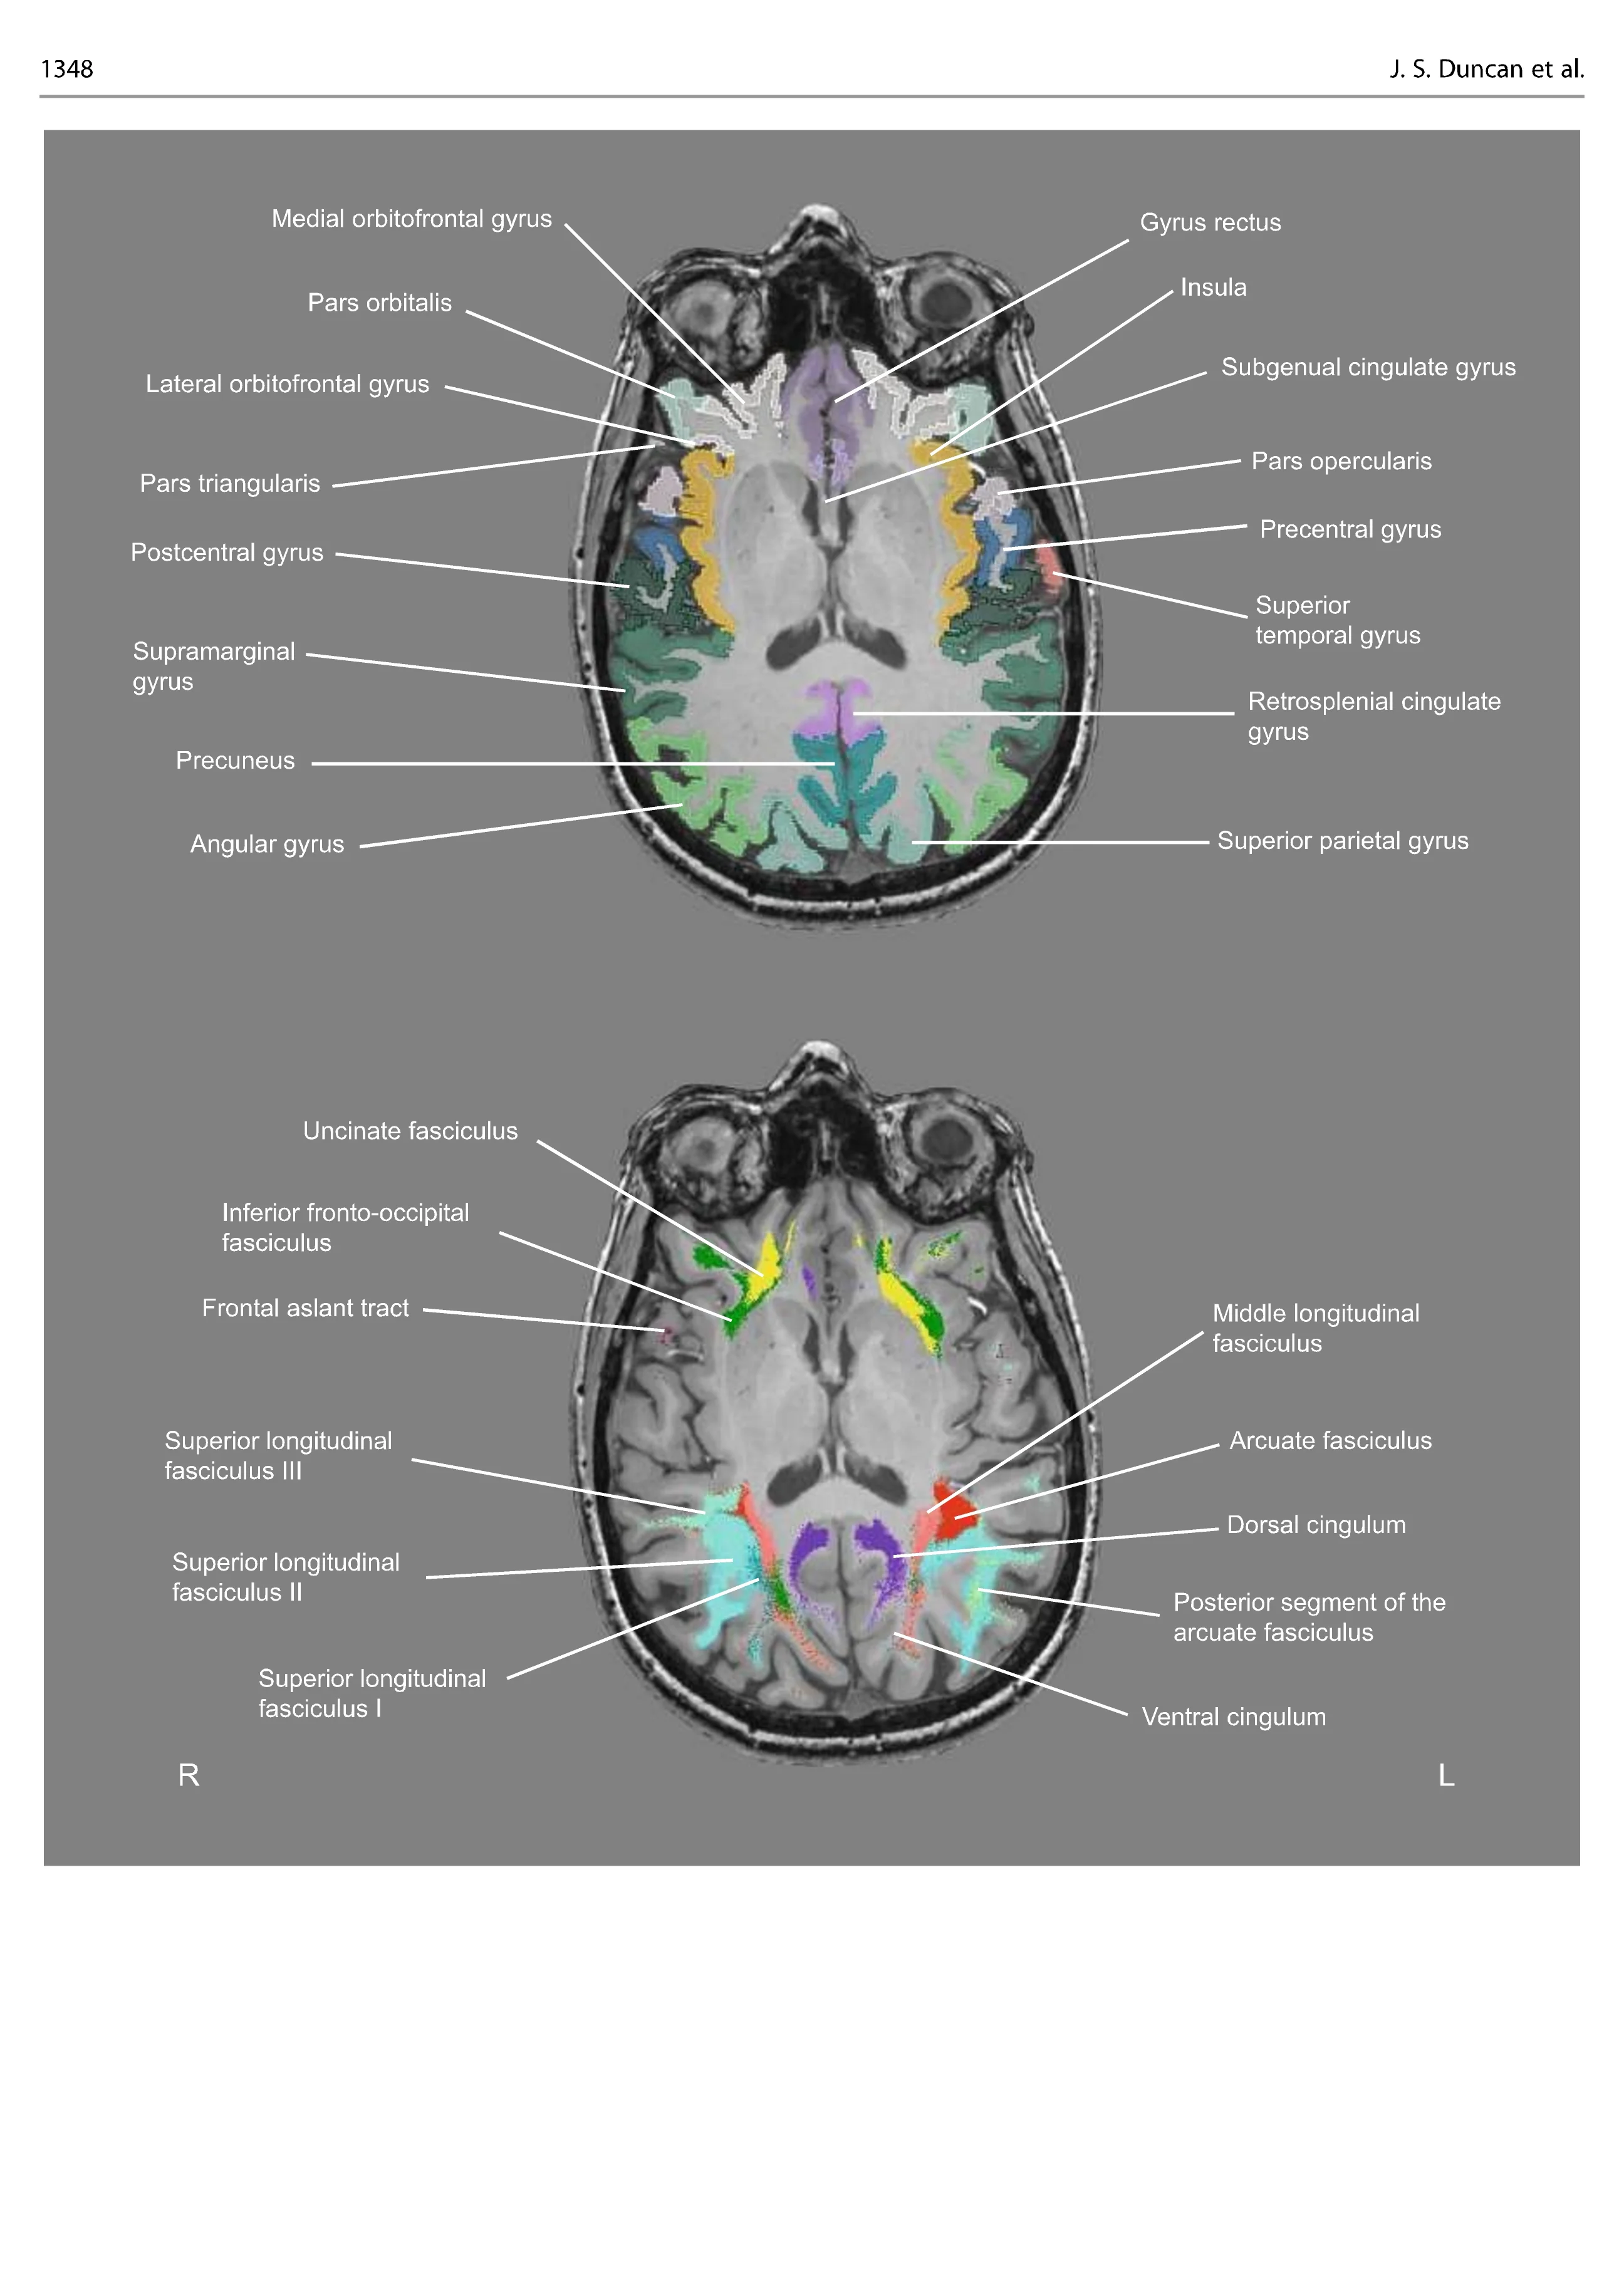

This atlas is based on a high-quality MRI of a healthy subject which resembles the type of imaging is regularly available to clinicians. It is structured in sections (cortical anatomy, subcortical anatomy, and network anatomy) that are intended to guide clinicians from the classical cortical paradigms into a network neuroscience perspective. The 2D orthogonal slices are organized in two orientations:

The second part shows the same brain cut in 2D orthogonal slices (axial, coronal, sagittal) with a raw T1-weighted image, accompanied by a labelled image showing the gross anatomy of the brain and grey matter structures and, also, the labelled white matter tracts in that slice. This is particularly relevant for neurosurgeons, who will be able to appreciate before planning a resection the relationship between each tract’s trajectory and the gray matter. This will also benefit neurologists, enabling clarity as to how single lesions can cause multiple disconnection and impact on different functions and behaviours.

The third part demonstrates the 3D anatomy of the major white matter tracts in the brain, to indicate how distant lesions can impact the same function.